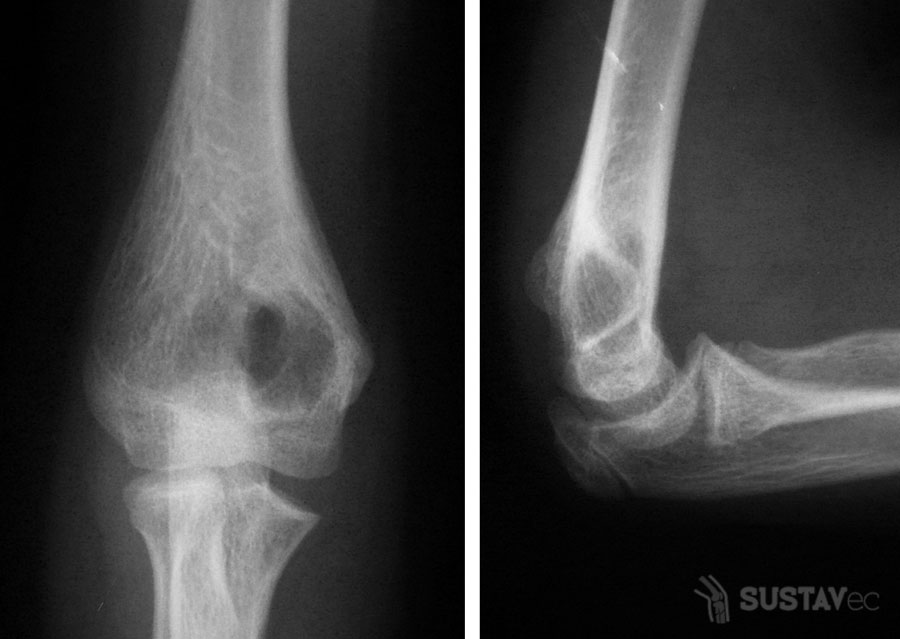

Перелом головки лучевой кости

Сложный локтевой сустав образуют три кости: плечевая связана с локтевой и лучевой костью предплечья. Все три элемента окружены фиброзной капсулой.

Фрактура головки лучевой кости — это повреждение участка, который находится вблизи локтевого сустава. Данная травма является одной из наиболее часто встречающихся патологий локтевого сустава у взрослых. Перелом происходит, когда пациент падает на вытянутую, слегка согнутую руку. Реже фрактура головки лучевой кости случается во время прямого падения либо удара локтя.

Вслучае сложных переломов ортопед должен рассчитывать на появление сопутствующих травм суставной капсулы и связок, что в свою очередь оказывает влияние на дальнейшее лечение и сроки выздоровления пациента.

Привычными симптомами данной патологии являются боли в локте, а также отеки на внешней стороне локтя. Кроме того, ограничена подвижность локтевого сустава.

Головка лучевой кости — это важный элемент локтевого сустава. Её вращение вокруг своей оси обеспечивает пронацию и супинацию предплечья.